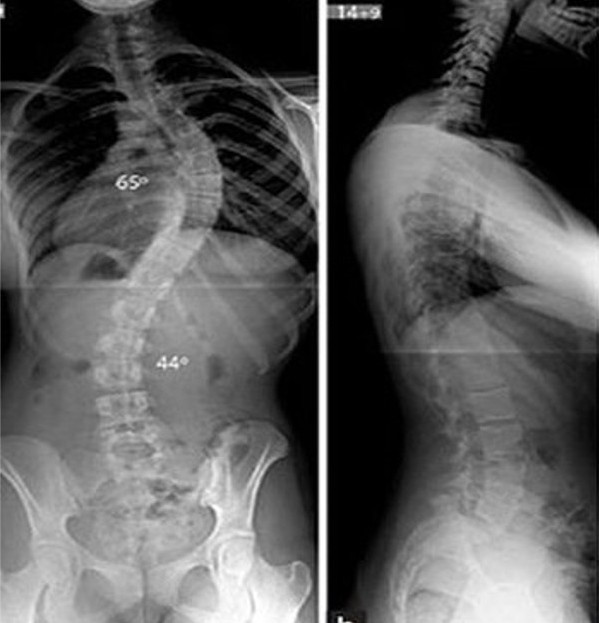

Tùy mức độ vẹo cột sống, bác sĩ sẽ chỉ định phương pháp điều trị phù hợp. Ảnh: BVCC

Trường hợp khác là N.K.Ch., 15 tuổi ở Hà Tĩnh, bị cong vẹo cột sống từ nhiều năm nhưng cha mẹ không hay biết. Mãi đến kỳ nghỉ hè, khi ở nhà và buộc tóc cao, phụ huynh mới nhận thấy dấu hiệu bất thường ở cột sống của con. Hình ảnh X-quang cho thấy cột sống của Ch. uốn cong rõ hình chữ S. Các bác sĩ đánh giá mức lệch lên tới 64 độ, buộc phải tiến hành phẫu thuật để điều chỉnh và ngăn tình trạng tiến triển nặng hơn.

Về phương pháp điều trị, theo chuyên gia của Bệnh viện Hữu nghị Việt Đức, tùy vào mức độ nặng nhẹ, độ tuổi, tốc độ tiến triển, chất lượng xương và chức năng tim phổi của trẻ, các bác sĩ sẽ lựa chọn phương án phù hợp. Với những trường hợp vẹo cột sống nhỏ, ít nguy cơ tiến triển, trẻ có thể được theo dõi định kỳ mỗi 6 tháng hoặc 1 năm.

Nếu đường cong cột sống lớn và có nguy cơ tăng tiến, các biện pháp như bó bột hoặc đeo áo nẹp sẽ giúp ngăn chặn tình trạng cong thêm, đồng thời trì hoãn thời điểm phẫu thuật để cột sống phát triển tối đa. Trong những trường hợp vẹo tiến triển nhanh, vẹo nặng và nguy cơ cao, phẫu thuật được xem là phương án hiệu quả nhất.